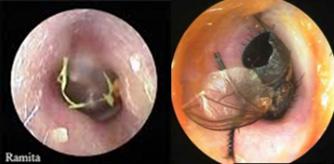

Figura 22. Colesteatoma adquirido primario de oreja izquierda. Pequeña erosión epitimpánica con colesteatoma. La piel que rodea la erosión está hiperémica y evertida.